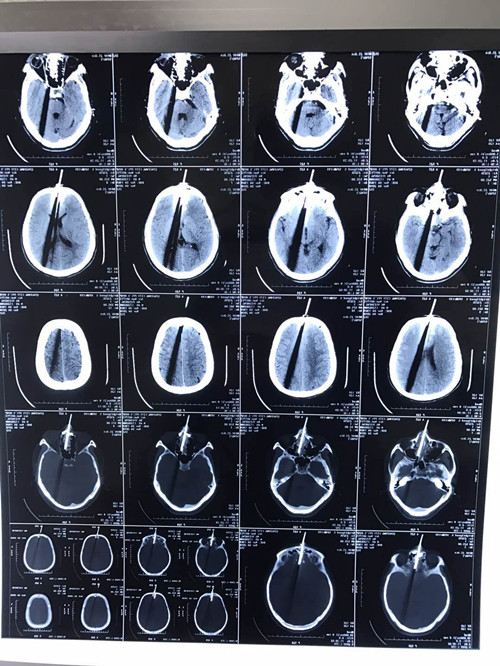

从病史中了解到,54岁的患者在早上10:30左右使用电锯工作时,突发电锯破碎,飞轮直接“蹿蹦”到了颜面部,瞬间“刨”掉了大半个鼻子,颜面如同劈开一般,皮肉外翻,血流不止。马先生被立即送到当地医院,头颅CT提示电锯已嵌入颅内,为求进一步治疗转我院。查体发现颜面正中处有一齿状刀轮嵌入,前额、鼻部、上颌、上下唇广泛纵向裂伤,刀轮嵌入骨内,创面污染严重,创缘不规则,伤口不断出血。考虑到患者已受伤近7小时,且已出现意识状态改变,需要紧急手术治疗。于是,古医生积极处理创面、建立静脉通路后予以抗感染、止血等治疗的同时,立即启动创伤救治程序;积极完善手术准备,由急诊科住院总党医师建立中心静脉通路,并请神经外科、头颈耳鼻喉科及西安交通大学口腔医院多学科会诊,共同制定手术方案,开启多学科共同诊治模式。经过近8小时的紧张手术,患者头部异物顺利取出、颜面创伤缝合处理完毕,转入急诊ICU继续治疗。今晨查房时患者神志转清,生命体征平稳,肢体活动未见明显异常。